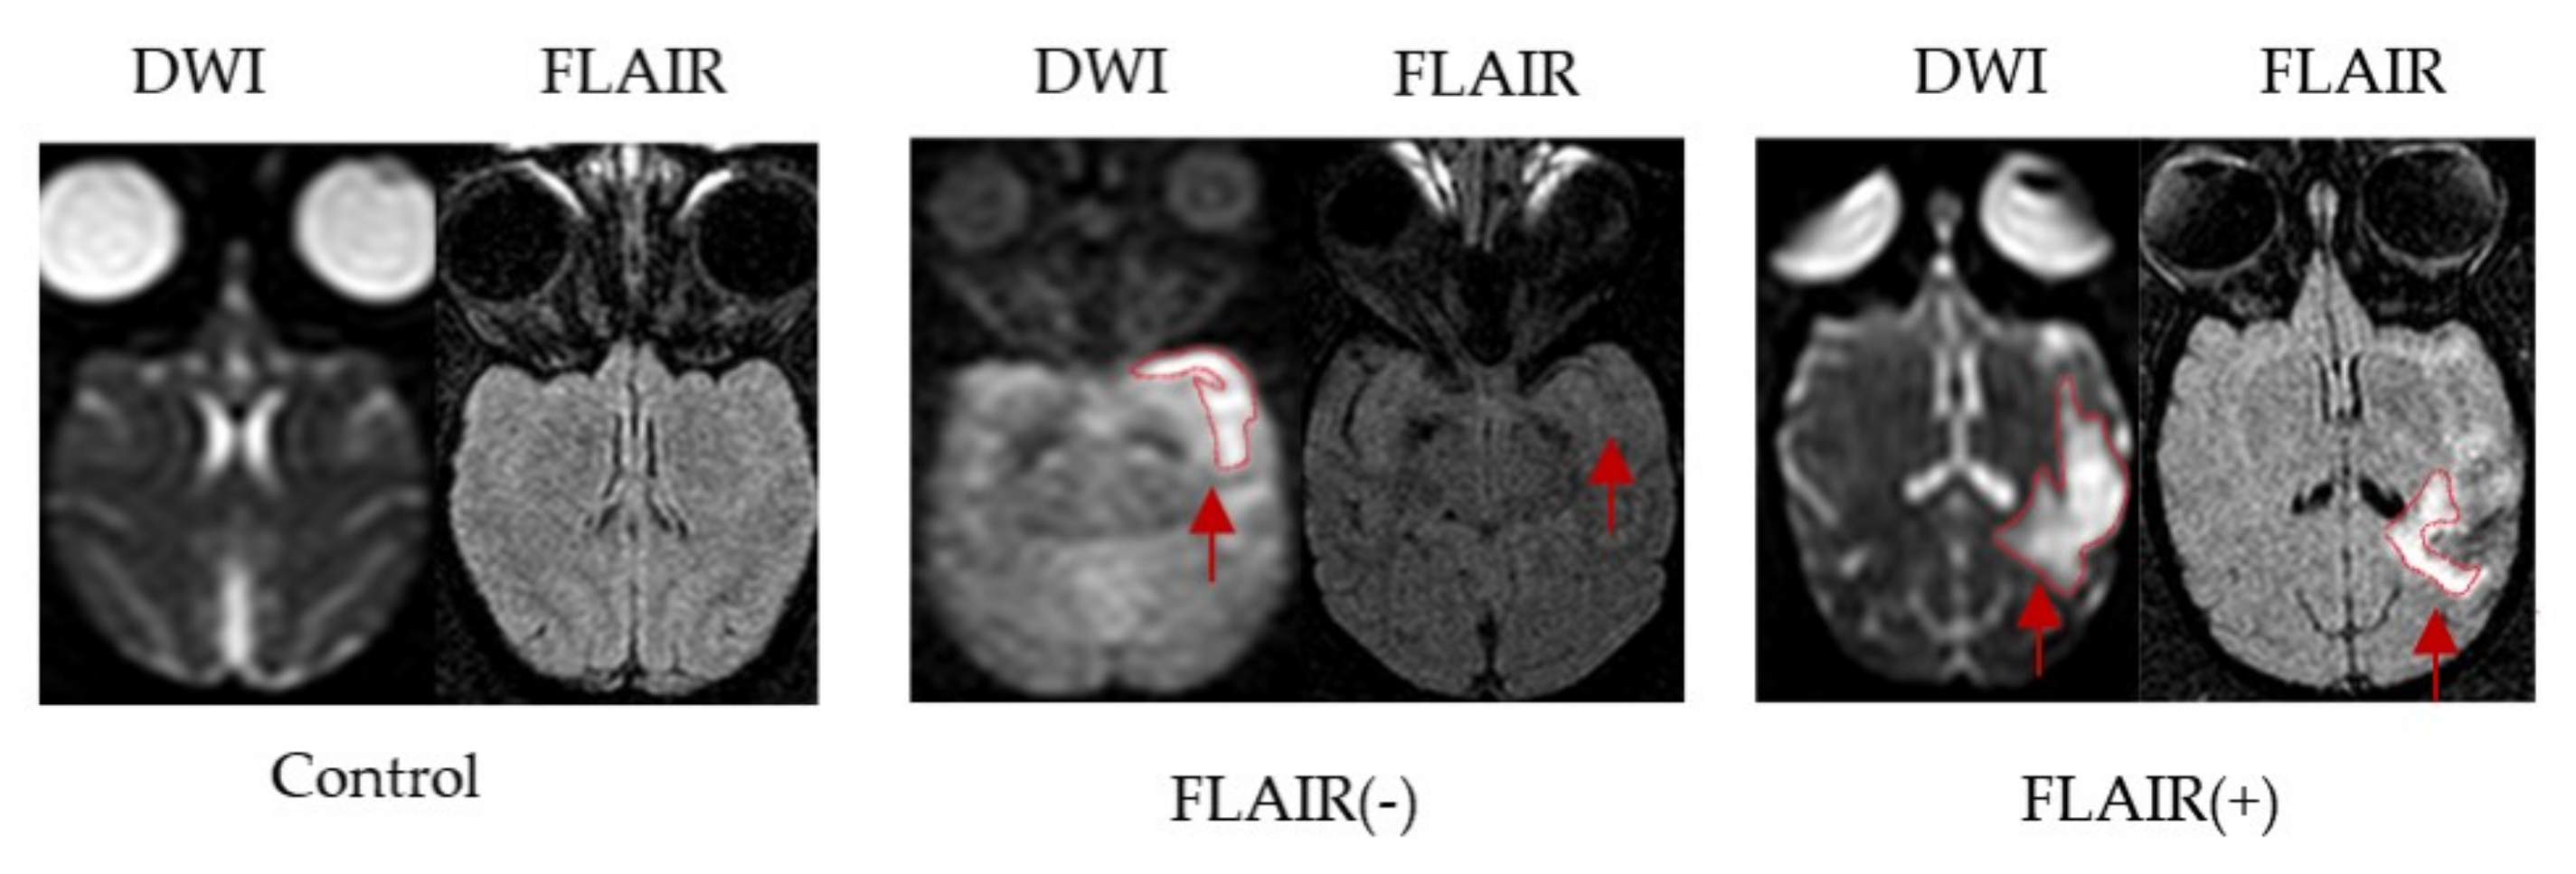

The MRI and neurological examination of three healthy control monkeys were normal. The total experiment time from MCAO to MRI completion and blood collection was approximately 2 h. Successful establishment of the stroke model was confirmed by brain parenchyma hyperintensity on DWI and the presence of neurological deficits. The stroke model was successfully established in 8 of the 13 monkeys and failed in 5 monkeys. Two monkeys died of cerebral herniation, one died of intestinal obstruction and infection, and two monkeys had no neurological deficits and no infarcts on MRI. Based on the FLAIR signal on MRI findings, eight postoperative cynomolgus macaques for the MACO model were divided into a FLAIR (−) group (N = 4) and a FLAIR (+) group (N = 4) (Figure 2).

Figure 2.

Brain MRI images of the MCAO model in cynomolgus macaques. Representative images of infarction lesions on DWI and FLAIR in cynomolgus macaque brains after MCAO (red arrow).